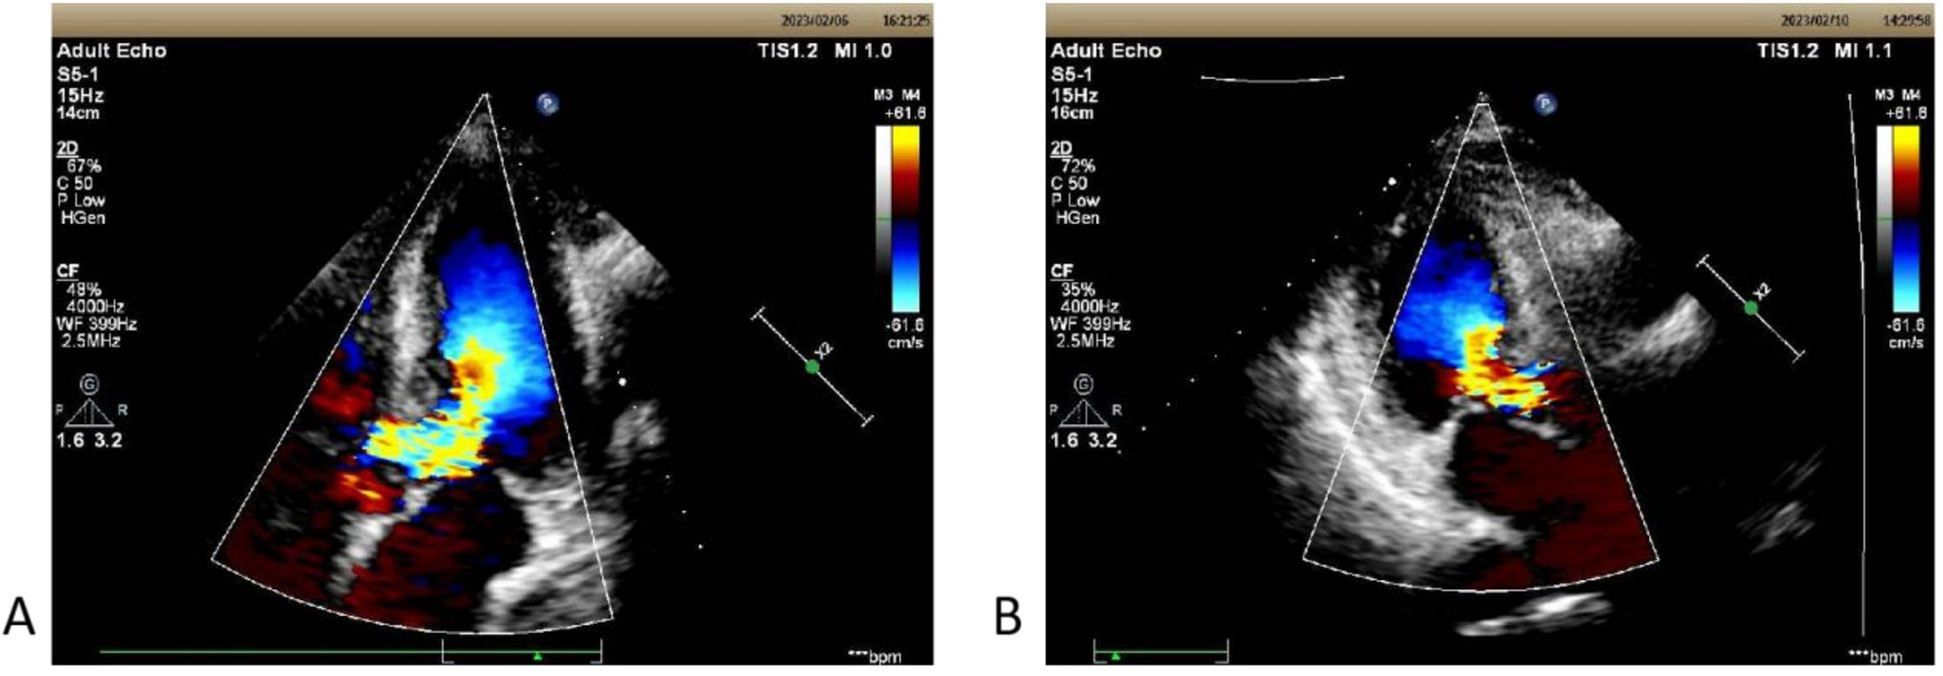

Due to the complications of bradyarrhythmia and sinus arrests, the use of β-blockers or calcium channel antagonists for alleviating obstruction was relatively contraindicated. After comprehensive consideration, it was determined that dual-chamber pacemaker implantation could potentially alleviate the obstruction by altering the pacing sequence of the cardiac chambers and interventricular septum, as well as improve the ventricular rate. During the early stages of hospitalization, treatments including potassium reduction, glucose control, diuresis, and myocardial nutrition significantly improved the patient's general condition. With the consent of the patient and her family, a dual-chamber pacemaker was implanted on February 7, 2023. Under local anesthesia, atrial and ventricular electrodes were successfully fixed to the right atrial appendage and the right ventricular apex via the superior vena cava, operating in DDD mode. On third postoperative day, a repeat transthoracic echocardiogram revealed a significant decrease in the peak instantaneous gradient at the basal left ventricular segment from 111 to 24 mmHg, with the SAM of the mitral valve no longer present, and the maximum flow velocity of the LVOT reduced to 244 cm/s (Figure 1). The repeat holter indicated that pacemaker working well, pacing heart rate accounting for approximately 17.5% of the total heartbeats, with an average heart rate of 67 bpm, a minimum heart rate of 59 bpm, and no instances of sinus pause were observed (Figure 2). Additionally, the BNP level decreased to 48.59 pg/ml on the day before discharge. The patient continued taking metoprolol after discharge. Following a 2.5-month post-discharge follow-up, the patient's general condition remained stable, with a cardiac rate of 77 bpm and a maximum rate of 87 bpm. Her BNP level was 81.11 pg/ml, echocardiographic showed resting LVOT forward flow velocity: 244 cm/s.

Figure 1

(A) The echocardiographic view of patient 1 before operation with septal hypertrophy measuring 1.60 cm. Severe left ventricular outflow tract obstruction with increased blood flow velocity in the left ventricular outflow tract at rest, maximum flow velocity of 528 cm/s, maximum pressure gradient of 111 mmHg, and mean pressure gradient of 51 mmHg. (B) On the third postoperative day, the second echocardiography showed: The left ventricular outflow tract velocity with a maximum flow velocity of 244 cm/s and a maximum pressure gradient of 24 mmHg.